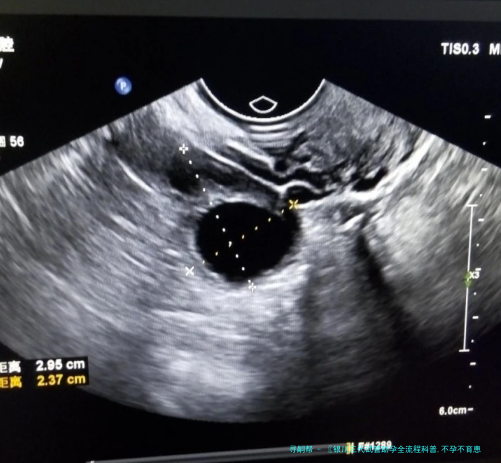

胚胎移植前,病患须要接收子宫腔内环境检查。如果察觉左右成功率的疾病,应当先将胚胎冷冻保存,等病症治愈后再进行移植。

当子宫内部环形境和内分泌系统都调节到最佳状态后,医生才会进行胚胎移植。移植过程时间较短,一般来说不需要,患者可能会有轻微不适感。

医生通过经阴道或经肚子形式将筛查出的健康胚胎植入子宫内。这一步骤需要精确操作,保障胚胎被放在理想座位。